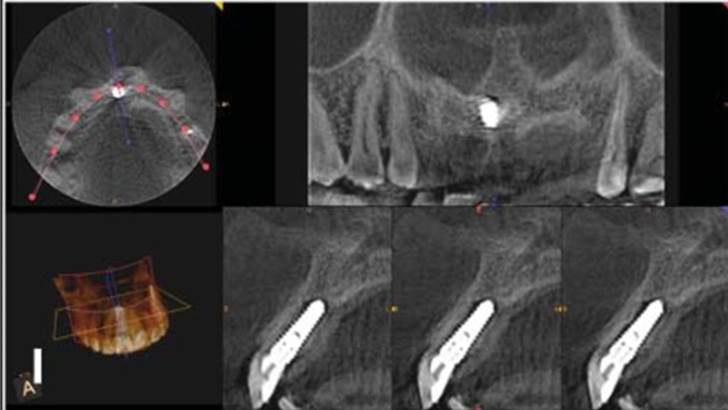

Clinical case: Bone filling into the bottom of deepest thread at 8.0mm AnyRidge fixture

- Courtesy of Dr. Kwang Bum Park -

Keywords

AnyRidge, Knifethread ,extraction socket, ,initial stability ,Allograft, ,osseointegratio ,Dr. Kwang Bum Park, , Mandibular, Single replacement, AnyRidge, Mega-oss,

Products used

Implant system-AnyRidge, Regeneration-Mega-Oss